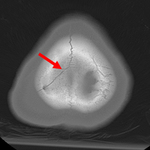

Fratura parietal linear sem depressão

Do acervo de aulas de Demetrios Demetriades, Division of Trauma and Surgical Intensive Care, LAC/USC Trauma Center, Keck School of Medicine da USC; usada com permissão